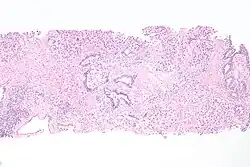

The Paris System for reporting urinary cytology, version 2.0, ranging from negative to positive for high grade urothelial carcinoma (HGUC).[11]

11. ^ - Image by Mikael Häggström. Reference: Wojcik, EM; Kurtycz, DFI; Rosenthal, DL (2022). "We'll always have Paris The Paris System for Reporting Urinary Cytology 2022". J Am Soc Cytopathol. 11 (2): 62–66. doi:10.1016/j.jasc.2021.12.003. PMID 35094954. S2CID 246429500.